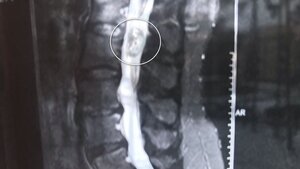

Эксперт отметила, что в текущий момент на рентгеновских снимках зумеров выявляется не более двух "восьмерок", в отличие от традиционных четырех. При этом они зачастую вырастают кривыми и косыми, что потребует их дорогостоящего удаления в будущем.